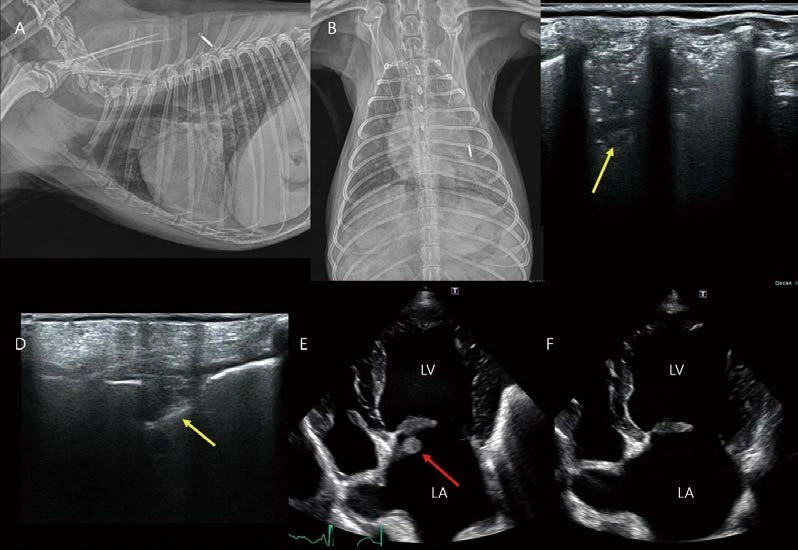

이 환자 역시 급성 기력저하로 응급 내원하였습니다. 흉부방사선 검사에서 심비대(좌심방 및 좌심이 확장)가 관찰되는데, 심한 심비대에 비해 폐혈관이 얇게 관찰됩니다(A, B). 심초음파에서 심낭수가 ACVIM stage C 이상의 MMVD 소견이 관찰되고, 종괴 또는 혈전 등은 관찰되지 않았습니다(C). MMVD에 의한 left atrial tear, pericardial effusion 상태로 생각되었습니다. 심낭수는 관찰되나, cardiac tamponade 소견은 아직 유의적이지 않았기 때문에, 보호자님의 선택에 따라 응급 입원 모니터링하였는데, 다행히 12시간 정도의 시간 뒤에 심낭수 천자 없이도 심낭수 및 환자의 전반적인 상태가 개선되었습니다. 이 후 흉부방사선 검사(D, perihilar region의 소량의 CPE 상태)와 비교해 보면(특히 폐전엽 및 perihilar region의 폐혈관 직경을 평가해 보면), 심낭수 발생 시에는 lung vessels의 직경이 얇아 보이는 상태, 즉 pulmonary hypoperfusion 상태임을 알 수 있습니다. 심장 질환 평가 시, 폐혈관도 함께 해석하면 환자의 현재 상태 평가에 큰 도움이 됩니다.

A2. 11살 중성화 수컷 3.25kg Poodle이 호흡곤란으로 내원하였습니다. 흉부방사선 검사에서 왼쪽 폐 전반적으로 침윤 밀도가 관찰됩니다(A, B). 폐초음파에서 shred sign을 포함한 광범위 폐침윤 영역 (C, 폐렴 고려)과 wedge 모양의 작은 저에코 영역(D, lung infarction 고려)이 관찰됩니다. 심초음파에서 septal mitral valve 후방으로 pedunculated 양상으로 움직이는 혈전 음영이 관찰됩니다. 혈액 검사에서 CRP 206 D-dimer 5.5로 매우 높았고, NT proBNP는 500으로 정상 범위로 측정되었습니다. 환자는 폐렴으로 인한 thromboembolism 발생 상태로 생각됩니다. Mitral valve에 부착된 혈전은 폐렴 치료 6일째 해소되었습니다(F). Systemic disorders 환자의 심초음파에서 intracardiac thrombi, valvular thrombic vegetation이 관찰되는 경우가 있습니다. 노령의 소형견에서 MMVD는 흔합니다. 준임상적 단계일 수 있고, 중증의 MMVD라고 하더라도, Valvular changes가 발생할 수 있는 다른 질환이 동반되어 있을 수 있으므로, 종합적인 전신 평가가 추천됩니다.